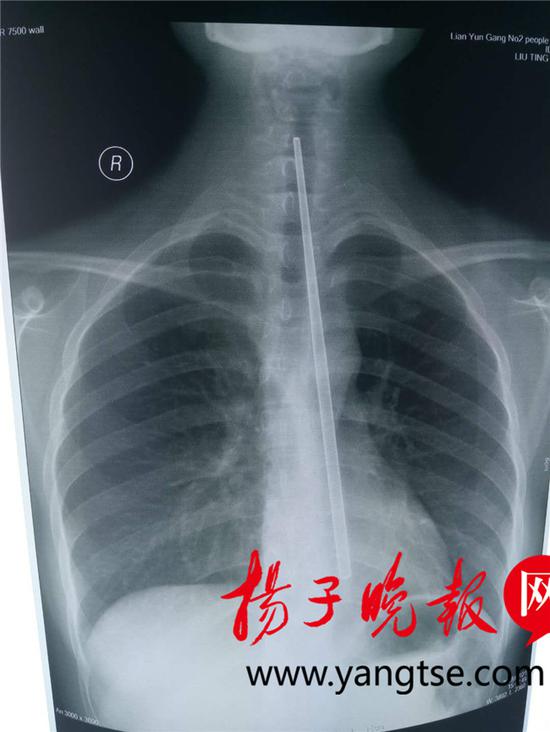

经联合会诊,消化科副主任医师张秀敏决定实施全麻,在胃镜下取筷子。但这需要患者禁食足够长的时间。5个小时后,当晚8时许,手术开始。此前,该院内镜中心护士长张琳在下午加班手术结束后,专程去超市购买了相同的金属筷。筷子很滑,只有浅浅的几道横纹可以作为着力点。

张琳和张秀敏医生抓紧时间,多次模拟手术,以尽可能提高一次性取出筷子的成功率。

手术正式开始后,钢筷被医护人员小心套住,拉至咽喉处。但因为筷子长度太长,且难以折弯,再次被卡住。

医护人员随后抬高患者下颌,同时压住筷子,快速同步操作,终于将整根筷子取出。

手术耗时约十分钟。